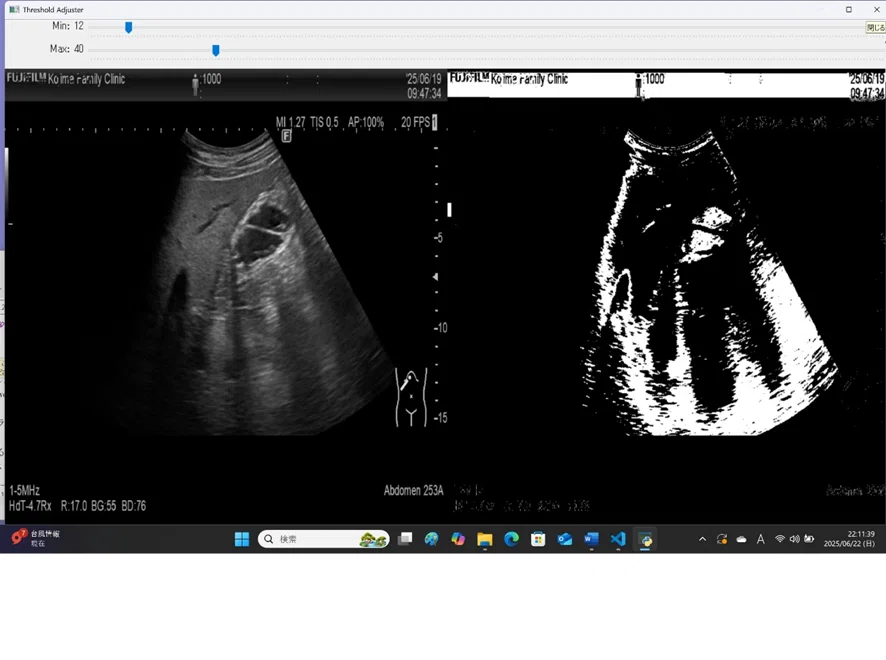

try.py(図では、左の元画像から、胃の部分が白く「マスク化」されるように、上のmax,minの閾値をスライダーで調整している)

そして、3D画像をつくり、その病変の臓器内の位置を示すための準備(ピクセル値の閾値を利用し白黒画像に変換する「マスク法」)の中心は、その閾値の決定にある。基本は、以前に書いたような、移った箇所のピクセル値を計測して域値設定の情報にする

さらに、これをもっと直感的にするように、たとえば、OpenCVのスライダーUIでしきい値を調整しながら、1枚の画像を2値化して確認できるPythonコード:try.py もいいかもしれない。

達成したシステム:threshold_viewer_flask どの閾値(マスク)を使用するといいのか、対象jpgファイル(例200枚)すべてをながめながら決定(閾値は全ファイル共通、ひとつだけ) app.py実行後、localhost (http://127.0.0.1:5000) にて描画: